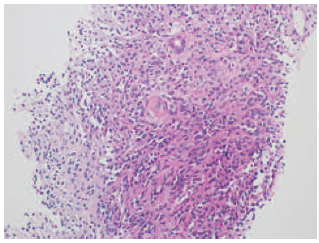

A biopsy of the transplanted kidney was conducted to elucidate the cause of transplant dysfunction. Two cores were taken from 2 separate areas. Histopathology showed neoplastic infiltration with proliferating spindle cells interspersed with vascular channels (Figure 2). Immunoperoxidase staining was positive for vascular marker CD31 and HHV-8 (Figure 3). A diagnosis of Kaposi sarcoma was rendered given the morphologic pattern and the immunohistochemical profile of a vascular neoplasm along with HHV-8 positivity. Epithelial markers (including AE1/AE3, MNF116, and epithelial membrane antigen) were negative in the neoplastic cells, eliminating the possibility of an epithelial neoplasm (eg, renal cell carcinoma). In addition, immunostaining tests for desmin, smooth muscle actin, S100, and HMB-45 were negative, thus excluding mesenchymal tumors (eg, angiomyolipoma). Light microscopy of the scant nonneoplastic cortical tissue showed 2 normal glomeruli without any evidence

of immune complex deposits. Although a mild lymphocytic interstitial infiltrate was present, there was no tubulitis, intimal arteritis, or peritubular capillaritis. C4d staining in the peritubular capillaries was negative. Hematopoietic markers including CD45, CD20, CD3, and CD5 showed a benign pattern, ruling out posttransplant lymphoproliferative disorders. No granulomas or viral inclusions were identified; viral markers for SV40 and Epstein-Barr virus were negative. Biopsy specimens of the hepatic lesions were obtained, and their histologic findings were also consistent with Kaposi sarcoma. Gastroscopy and colonoscopy did not reveal any lesions of Kaposi sarcoma.

Figure 2. Kidney Transplant Biopsy With Hematoxylin and Eosin Staining (×100) Showing Infiltrating Spindle Cells With Vascular Channels

Figure 3. Kidney Transplant Biopsy Showing Positive Immunohistochemical Staining (×400) for Human Herpes Virus 8